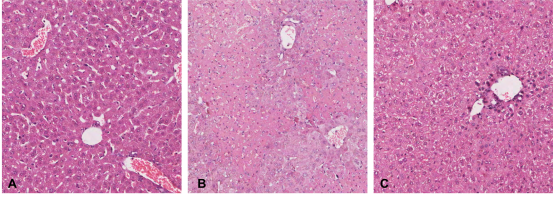

邓志华课题组查阅大量文献资料����,发现肝星状细胞(HSC)在肝纤维化中发挥关键作用�����,此外近年研究还发现HSC具有免疫细胞特征���,直接参与肝脏的免疫调控����,但由于HSC是肝脏的非实质细胞���,数量极少���,分离小鼠原代HSC非常困难���,限制了其研究进展���。课题组经过不断摸索研究����,运用OptiPrep分离液结合原位手工灌注法分离到BALB/c小鼠高纯度高得率的原代HSC��,倒置荧光显微镜下观察���:新分离的HSC呈圆形���,具有丰富的脂滴����,在328nm波长的紫外光激发下自发蓝绿色荧光��,逐渐从圆形变为梭形或星形����,培养7d后����,伸出细长的伪足���。原代HSC油红O染色阳性���,胞浆中的脂滴呈红色��,细胞核呈蓝色���,传2代后免疫细胞化学染色HSC完全表达α-SMA和Desmin����,自发活化����。课题组进一步将BALB/c来源的HSC与C57BL/6小鼠脾脏来源的Treg细胞共培养��,观察HSC对Treg的诱导作用���,异体活化的HSC可在体外呈剂量依赖性����、通过细胞-细胞直接接触方式诱导Treg增殖��,扩增的Treg可有效表达FoxP3��,在体外可有效抑制Teff细胞增殖���。为进一步证实扩增的Treg的免疫调节活性���,将扩增的Treg通过尾静脉注射到ConA诱导的AIH小鼠体内��,观察其对AIH小鼠受损肝脏的影响���,发现扩增的Treg可调节AIH小鼠脾脏Treg/Th17比例失衡��,肝脏炎症和肝细胞坏死明显减轻[图2]���,血清ALT����、AST水平IL-6��、TNFα����、IFN-γ水平降低���,发挥了良好的治疗作用��。该课题为寻找替代糖皮质激素/硫唑嘌呤治疗AIH的免疫细胞疗法提供了可靠的实验研究结果�����。

图2过继转移体外扩增的Treg细胞后AIH模型小鼠肝脏病理变化(A����:正常肝脏B����:AIH模型肝脏C����:过继转移Treg后肝脏)